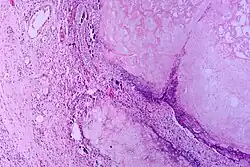

Pancreatic ductal adenocarcinoma

Pancreatic Ductal Adenocarcinoma (PDAC) is one of the most lethal cancers and has an expected survival of five years.[11] Pancreatic adenocarcinoma cells resemble pancreatic ductal cells. Both cell groups show tubule formation, cuboidal shape, and ductal markers. Additionally, acinar and endocrine cells have often been found in many of these cancers, demonstrating plasticity and the possibility that the initial target cells are pancreas progenitor cells.[3] Moreover, human tumors usually go with lower-grade lesions that are called pancreatic intraepithelial neoplasias (PanINs) and are in ducts. Because these lesions are in ducts, this means that it is possible that the beginning target cells are ductal cells.